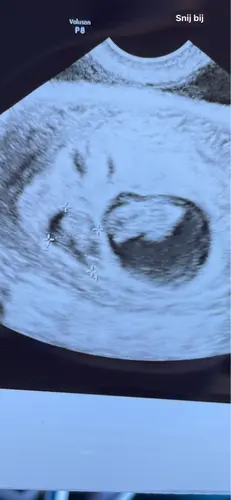

Hey! Heb ik ook gehad. de gehele zwangerschap bleef eentje kleiner + kleinere vruchtzak. Uiteindelijk kwamen ze bij mij erachter dat dit kwam doordat de kleinste maar 2 bloedvaten in zijn navelstreng had zitten. Uiteindelijk is alles goed gekomen. Hadden 1 kilo en 3cm verschil bij de geboorte. Nu 2 jaar later, 1,5 kilo en 5 cm馃槀

Ik vind het erg spannend. Het verschil in lengte is klein (1 dag) maar de zak van baby A was wel 2 a 3x zo groot als Baby B. Ik merkte dat de VK het zorgelijk vond.. poe! Ik vind het heftig. Fijn om te horen dat er positieve uitkomsten zijn